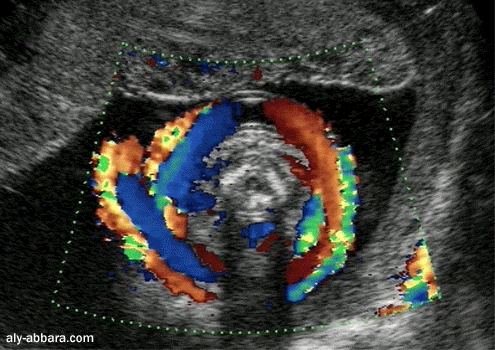

Circulaire péri-cervicale du cordon ombilical fœtal

Il s'agit d'une grossesse de 26 semaines d'aménorrhée

Parfois on peut observer la présence de multiple circulaires du cordon ombilical

(2, 3, voir 4 ou 5)